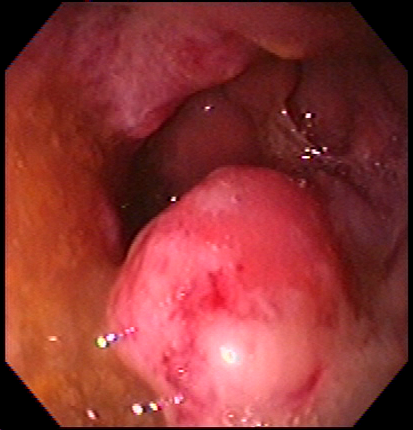

Feto cara cara2 Feto Oreja manos carita bebe Barret Barrett1 Pólipo Diverticulos Cancer rectal Transverso Duodeno Rayos%20x.jpg